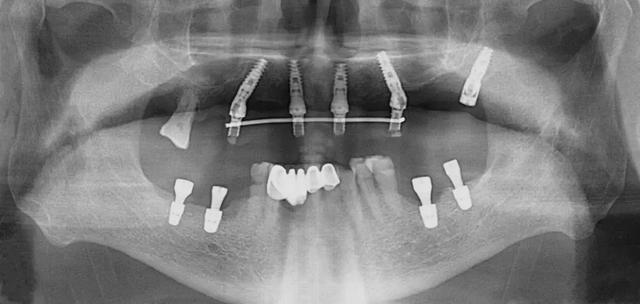

口腔科李德仁主任為老人仔細檢查了口腔情況,由于缺牙時間太久,牙床骨量極少,正常的種植修復需要植骨,手術創(chuàng)傷大而且半年后才能鑲牙吃飯。建議他進行數(shù)字化導板種植,可以不用植骨而且當天就能戴牙吃飯,手術簡單,創(chuàng)傷小。老人和孩子很信任的接受了李主任的種植方案:上牙床種植5顆,下牙床種植4顆,當天戴牙吃飯。

下午2點開始手術,歷經(jīng)90分鐘,一共植入9顆種植體,全程。下午7點用了10多分鐘就完成了假牙安裝,假牙與牙床渾然一體,像是重新長出的牙齒一般。

全口缺牙一日重建種植手術有以下優(yōu)點:使用CT導板定位,在骨量好的位置種植,一般不需植骨,手術創(chuàng)傷小,手術時間短,愈合快,基本上沒有疼痛。拔牙同時種植牙,當日戴臨時全口固定式假牙吃飯。